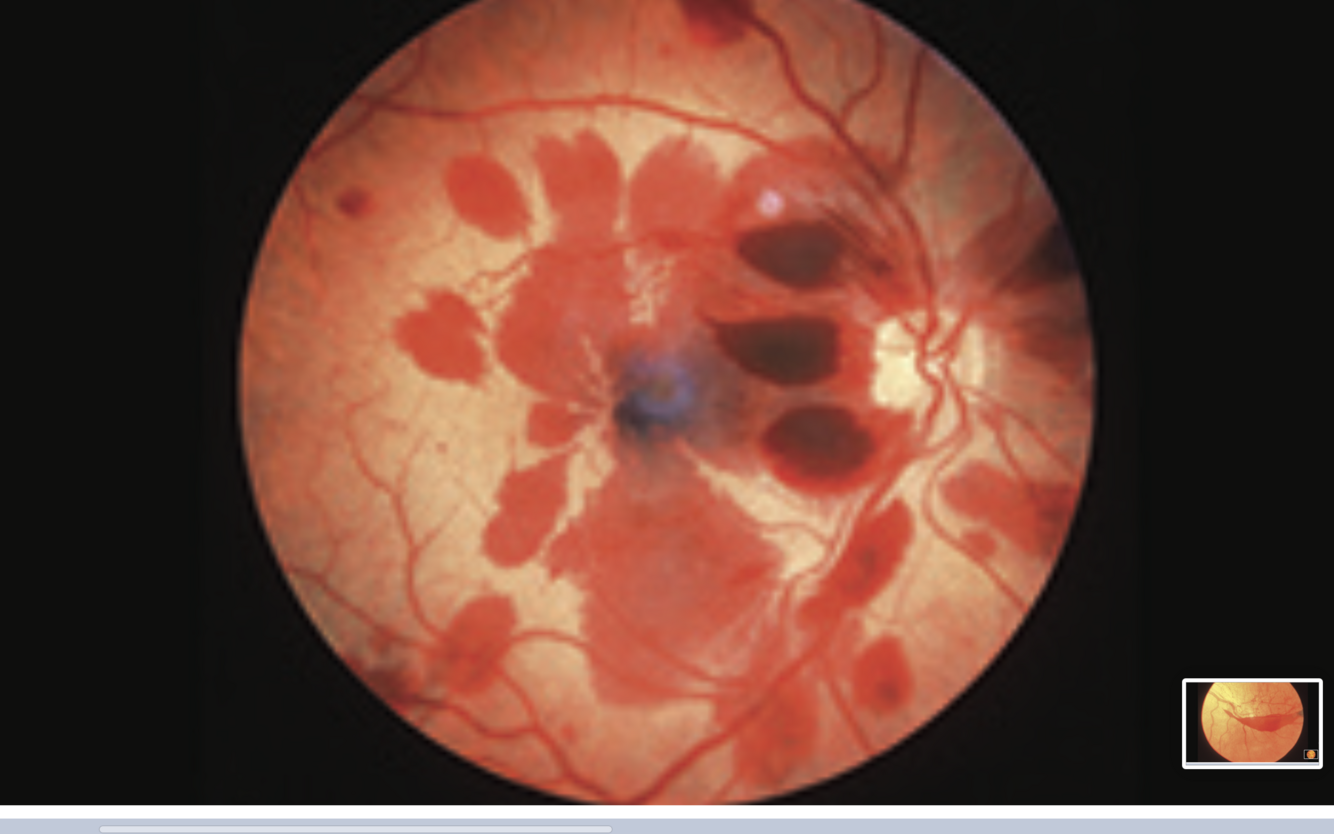

CRVO

- papilloedema

- tortuous and dilated branches of CRV

- retinal haemorrhages

- cotton wool spots